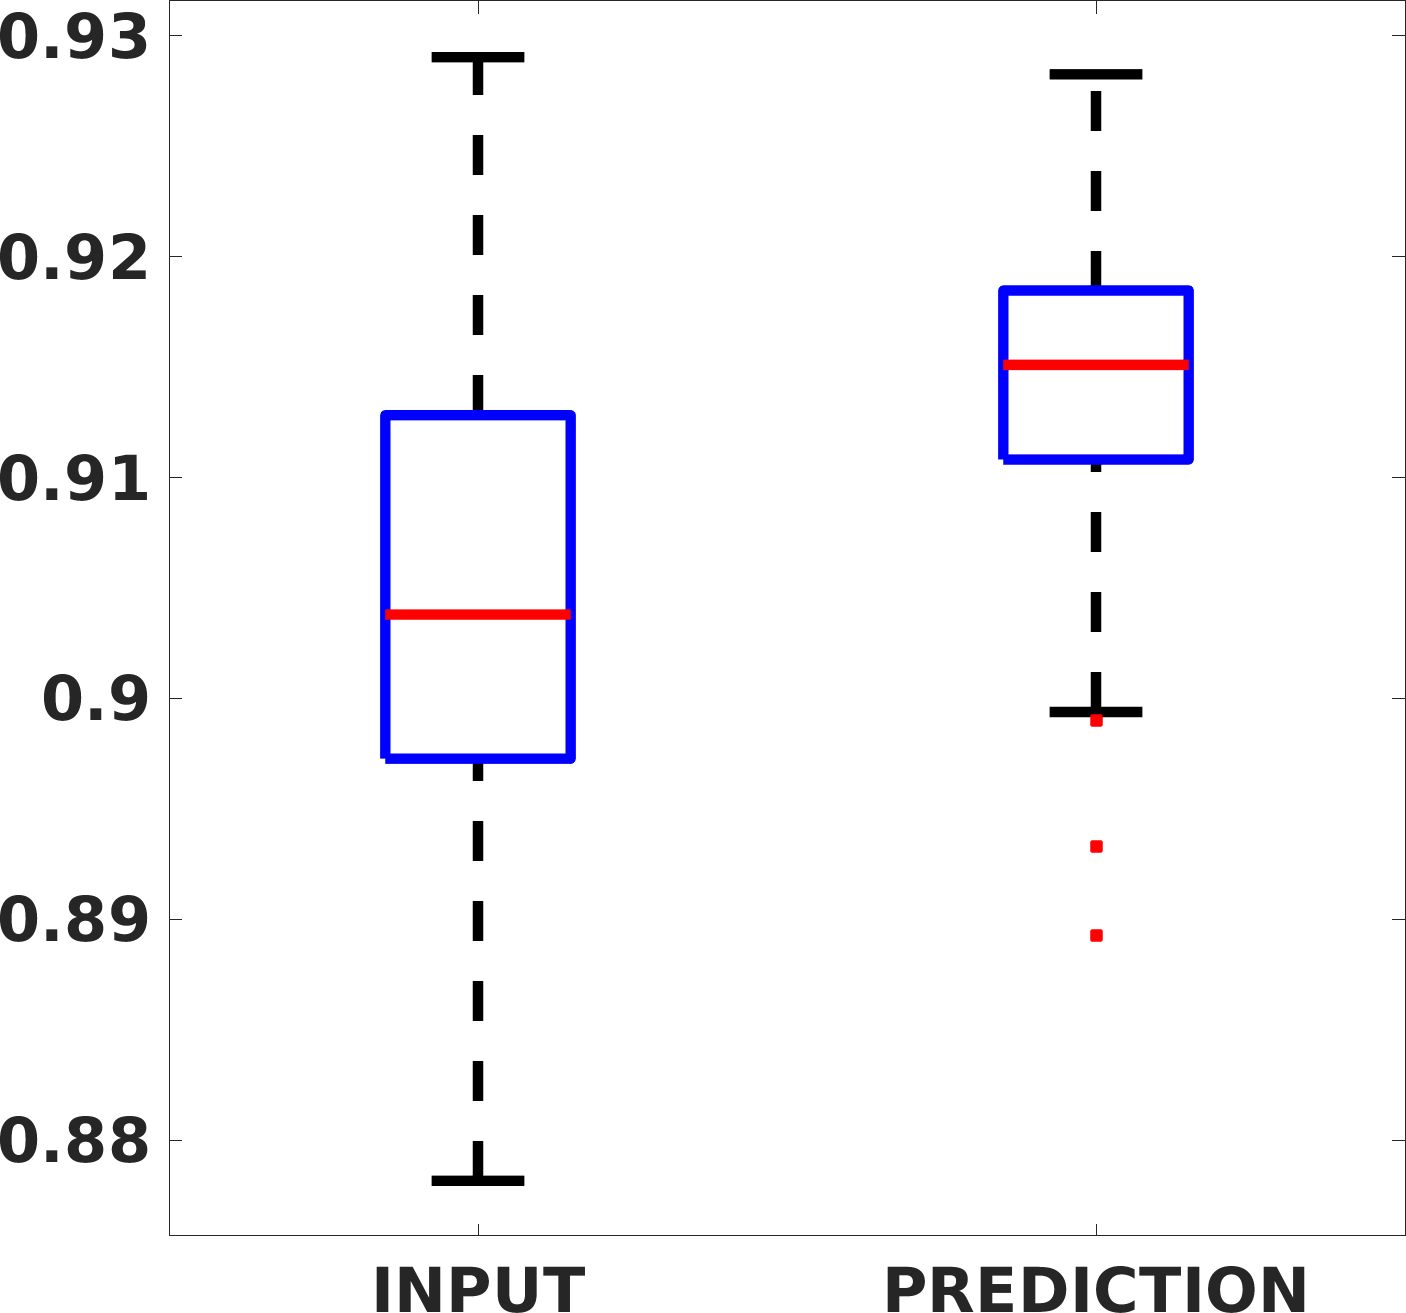

Fig. 8 shows the box plot of the SSIM (a-b-c, left) and MAE (a-b-c, right) quantitative metrics, as performed for PSNR metric. Also, these metrics show that our method improves the results of Cubic convolution both in terms of average value and variability. For example, the SSIM median value improves of on obstetric 4X images and the MAE median value improves of on cardiac 2X images.

Fig. 17 (left) shows the box plot of the quantitative metrics, comparing the target images with the prediction and the Cubic convolution, respectively. The PSNR metric is computed on a data set of 200 images, belonging to the same district, and with the same up-sampling factor. Analysing the obstetric anatomical district and concerning the corresponding raw images (Fig. 7 (a, left)), the denoising allows the network to significantly improve the results of the up-sampling and the prediction. In particular, comparing the target images with the predicted images, the median PSNR value of obstetric 2X denoised images is 51.8, compared to the median PSNR value of obstetric 2X raw images which is 36.9.

Fig. 17 (right) shows the histogram of the absolute value of the error with respect to the target, of the prediction and Cubic convolution respectively. This result shows that our framework increase of and (2X and 4X, respectively) the number of pixels where the prediction error is lower than 5, which is very similar to the target when visually analysing the images, and improved with respect to the learning framework applied to raw images. According to Fig. 18, our method improves the accuracy of Cubic convolution. For example, the SSIM increases of on cardiac 2X and the MAE increases of on abdominal 4X.